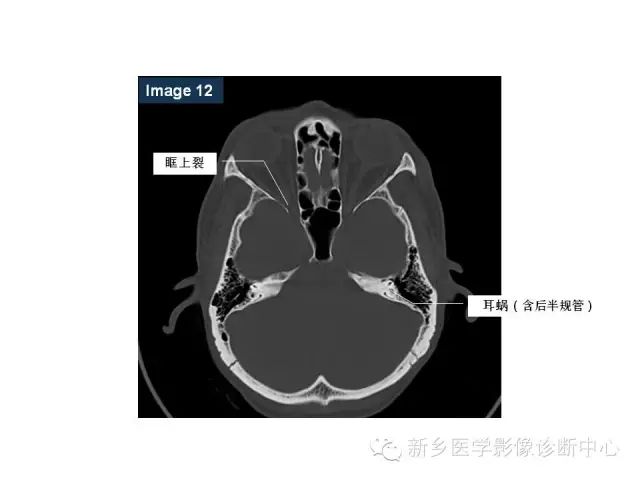

鼻咽部的详细解剖(含各个孔道)

来源:新乡医学影像诊断中心